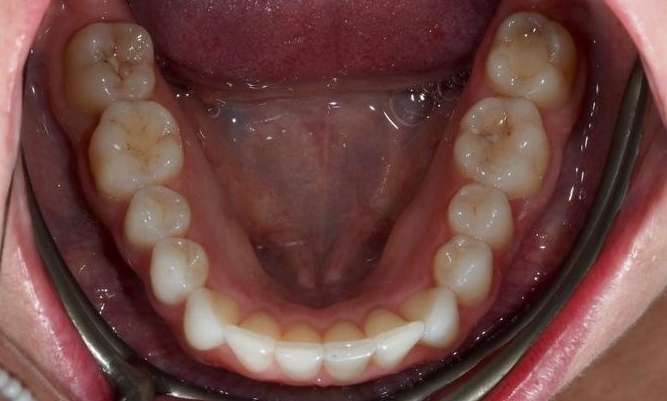

This patient presented with concerns about the damage his teeth had sustained from his bite and previous habits. His lower teeth had caused erosion and wear on the palatal surfaces and incisal edges of his upper front teeth. He was also concerned about the crowding of the lower front teeth. His primary goal was to create a more protected alignment and function of his teeth to support better oral health and longevity.

Due to a sensitive gag reflex, he first trialled nightly whitening trays for two weeks to assess whether he could tolerate aligner wear. This approach helped him proceed with ...